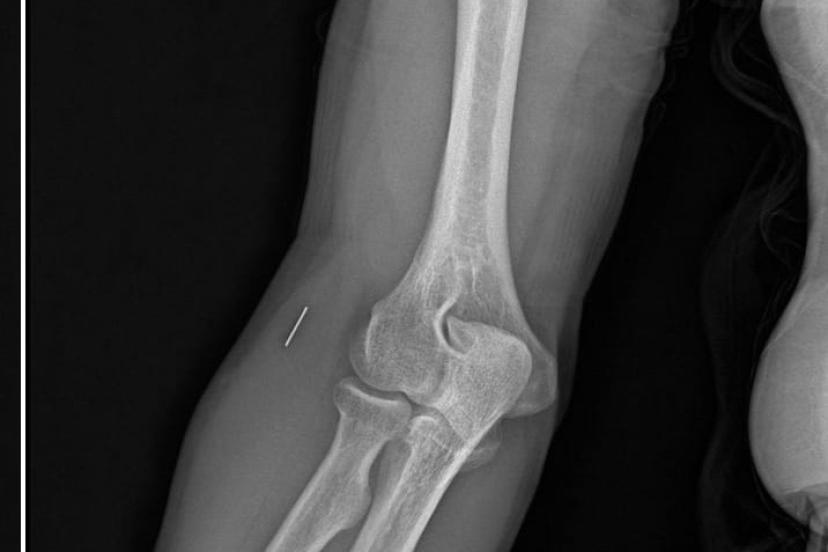

Öte yandan, ameliyatların ardından ağrıları devam eden Güleryüz’ün kolunda metal parça bulunduğu ve bu parçanın parmak bölgesinden dirseğe doğru ilerlediği öne sürüldü. Ayrıca, fabrikada temizlik personeli olarak çalışan Nurettin Güleryüz’ün hastane sürecinde işten çıkarıldığı da öğrenildi.

"Doktorlara bileğime doğru ağrılarım olduğunu sürekli ifade etmeme rağmen beni dinlemediler. Sonradan kolumda metal kaldığını öğrendik. Bunun ihmal olduğunu düşünüyoruz. Çünkü kola metal nasıl girebilir? Ben 9 aydır çalışamıyorum. Kalp rahatsızlığım sebebiyle yüzde 46 engelliyken şu anda yüzde 75 engelli durumuna düştüm. Erken emeklilik dilekçesi verdim ancak henüz sonuç gelmedi. Bu konuda çok mağdurum. Yetkililerin bunu duymasını istiyorum. Savcılığa suç duyurusunda bulunduk. Yaklaşık 9 aydır henüz soruşturma izni gelmedi. Süreci bekliyoruz, henüz dava açılmış değil. Kolumda bırakılan metal ilerliyor. Pazartesi günü bunun için de operasyon geçireceğim. Çıkarılıp çıkarılamayacağı net değil. Elimde titremelerim var, çalışamıyorum ve işveren tarafından işten çıkarıldım. Yetkililerden destek ve konunun incelenmesini talep ediyorum."